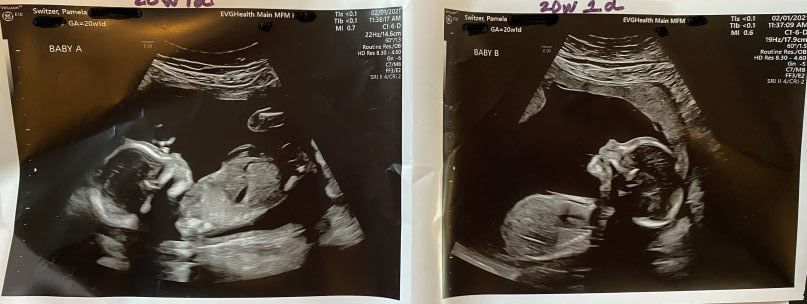

02/01/2021: 20w1d Twins Update | Dopplers worsen and Baby A (Joshua) now has a heart abnormality

Doppler crisis (again) + a new heart abnormality

After a weekend of contractions overnight all night on Saturday (which is highly unusual because the recommendation for stopping early contractions is hydrate and lie down with feet elevated) along with abdominal cramping, my medical team brought me in a day before my scheduled appointment.

While the fluid levels have improved, it feels like Baby A (Joshua) is deteriorating. He now has a problem with his heart along with his growth continuing to decline. Both babies now have abnormal MCA Dopplers in their Cerebral Arteries. I’ll come back in 48 hours on an empty stomach in case we have to do the dreaded surgery that might end Joshua’s life and potentially also Daniel’s. It’s our darkest hour thus far.